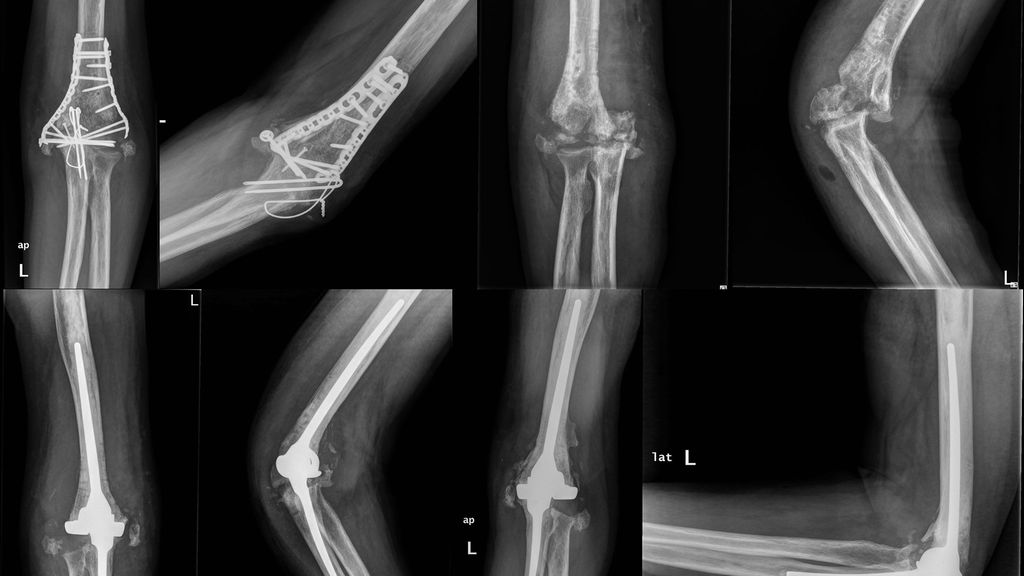

in 2 Fällen eine sehr schwere Steife bis 30°: in 1 Fall Steife in voller Streckung (Abb.1), im zweiten Fall Steife in 70°–80° Flexion

Abb. 1: Ein 42-jähriger männlicher Patient mit distaler Humeruspseudoarthrose und steifem Ellbogen in voller Streckung (a, b). Anamnestisch in dreimaligen Voreingriffen eine infektiöse Komplikation bekannt. Aufgrunddessen hier ein zweizeitiges Vorgehen. Im ersten Schritt die komplette Metallentfernung, Gewebeentnahme für Kultur und PCR-Untersuchung, radikales Debridement und ausgedehnte Arthrolyse (c, d). Bei nachgewiesener Infektionsfreiheit nun die Implantation einer Ellenbogenendoprothese (e, f). Röntgenkontrolle nach 6 Jahren (g, h)